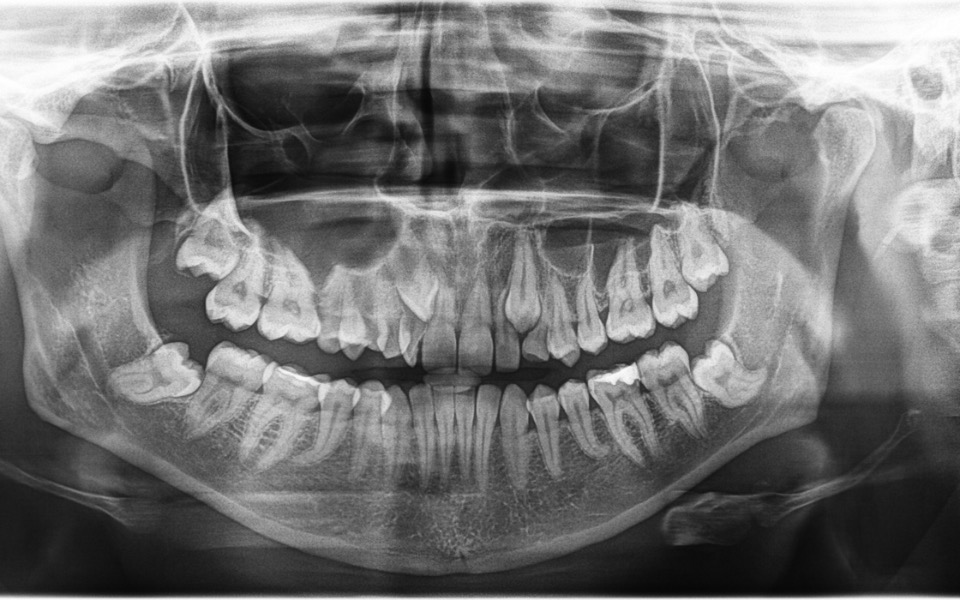

Zbieramy fundusze na leczenie ortodontyczne. Leczenie jest skomplikowane, ponieważ obejmuje usunięcie mlecznych zębów, oraz stałych, zatrzymanych, które powinny wejść w miejsce mlecznych. Dodatkowo czeka nas leczenie zębów, które są w bardzo złym stanie, niektóre patologicznie starte. Potrzebne będzie rownież założenie aparatu ortodontycznego a pózniej wizyty kontrolne.